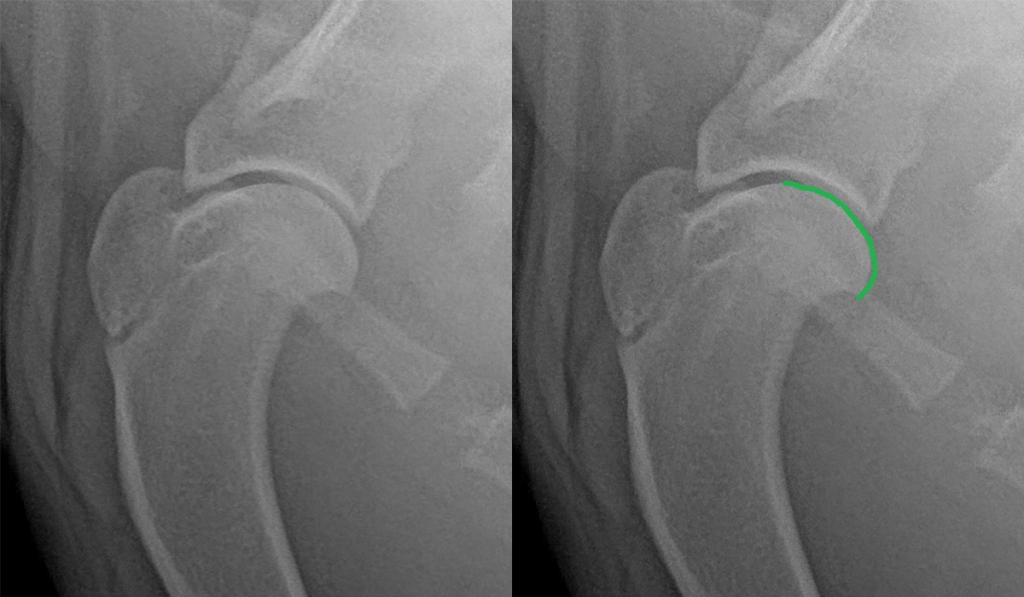

В норме поверхность головки плечевой кости без видимых прободений, эрозий и имеет ровную поверхность – отмечено зеленой линией.